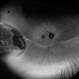

- Bilateral benign yellow dot maculopathy

- yellow dots, Autoflourescence

- A 37-year-old female patient presented for a routine eye examination. Her best-corrected visual acuity was 6/6 in both eyes. Fundus examination revealed multiple small yellow dots over the macula in both eyes. FAF imaging demonstrated characteristic hyperautofluorescence corresponding to these dots.